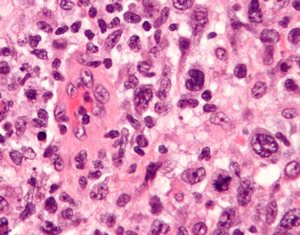

The ALCL includes four stages

Stage I(early disease)- The cancer is located in a single lymph, in one organ or area outside lymph node

Stage II- Means that it's locally advanced. This means the cancer is found in two or more lymph node regions on the same side of the diaphragm.

Stage III- Its advanced disease as 2 or more nodes are found above and below diaphragm

Stage IV- Widespread disease meaning that the lymphoma has spread beyond the lymph nodes and spread to one or more organs